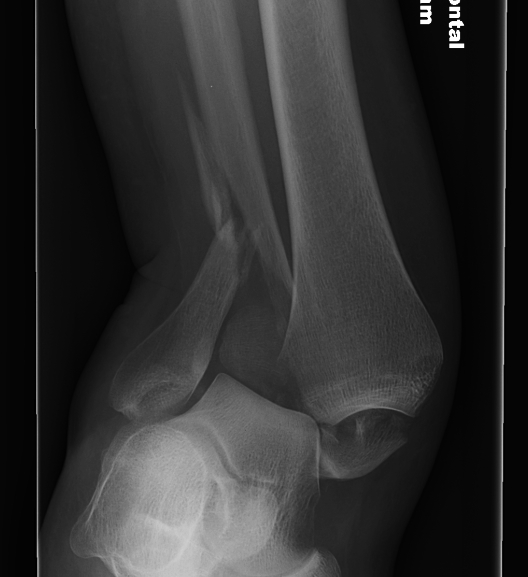

Ankle dislocation

Reduction under conscious sedation

- protects skin medially

- conscious sedation in emergency department

- well moulded cast

- unstable ankles need monitoring for loss of reduction

- can need external fixation to maintain position

Dislocationdislocationdislocation